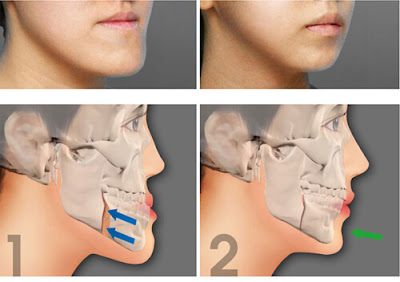

Cầu răng sứ: Cầu răng sứ là cách trồng răng giả bằng 2 cùi răng nằm hai bên chiếc răng bị mất. Nghĩa là bạn phải mài 2 cùi răng khỏe mạnh kế cạnh mới thực hiện được. Xét về lâu dài, cầu răng sứ không thể tránh gặp phải hiện tượng tiêu xương hàm do không có chân răng thay thế, điều này khiến khuôn mặt kém thẩm mỹ.

Cấy ghép implant: Phương pháp này được thực hiện bằng cách đặt trụ implant trực tiếp vào xương hàm mà không phải mài bất cứ cùi răng nào. Chân răng thay thế bằng trụ implant sẽ không xảy ra tình trạng tiêu xương hàm như làm cầu răng sứ. Theo các chuyên gia, chân răng nhân tạo có thể tốt và bền hơn răng thật.

Cầu răng sứ: Cầu răng sứ là cách trồng răng giả bằng 2 cùi răng nằm hai bên chiếc răng bị mất. Nghĩa là bạn phải mài 2 cùi răng khỏe mạnh kế cạnh mới thực hiện được. Xét về lâu dài, cầu răng sứ không thể tránh gặp phải hiện tượng tiêu xương hàm do không có chân răng thay thế, điều này khiến khuôn mặt kém thẩm mỹ.

Cấy ghép implant: Phương pháp này được thực hiện bằng cách đặt trụ implant trực tiếp vào xương hàm mà không phải mài bất cứ cùi răng nào. Chân răng thay thế bằng trụ implant sẽ không xảy ra tình trạng tiêu xương hàm như làm cầu răng sứ. Theo các chuyên gia, chân răng nhân tạo có thể tốt và bền hơn răng thật.

Ảnh hưởng tích cực: Tại vị trí mất răng, chỗ trống sẽ được lấp đầy và khả năng ăn nhai cùng tính thẩm mỹ sẽ được phục hồi. Những răng còn lại trên cung hàm có điểm tự vững chắc nên không lo sợ xảy ra tình trạng răng lung lay, xô lệch hay đổ nghiêng. Nếu chọn trồng răng hàm bằng cấy ghép implant còn có thể ngăn chặn tiêu xương hàm.